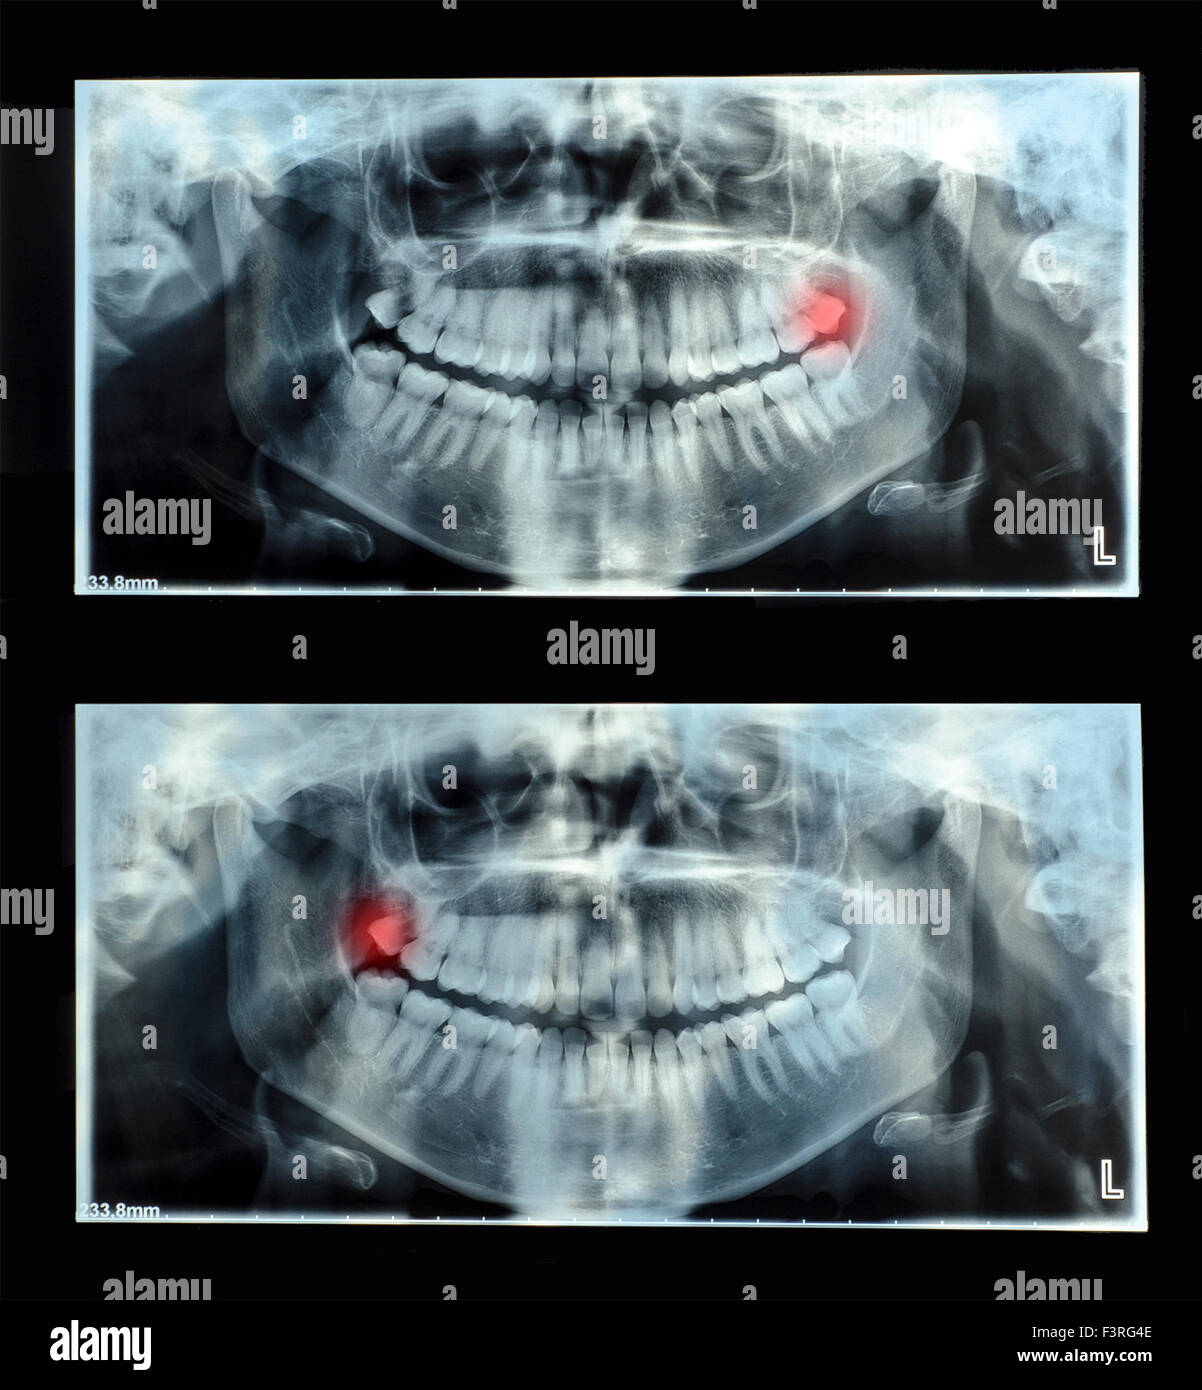

Horizontal Inflamed Wisdom Tooth On Panoramic Dental Tooth X-ray

www.dreamstime.comWISDOM TOOTH, X RAY Stock Photo - Alamy

www.dreamstime.comWISDOM TOOTH, X RAY Stock Photo - Alamy

www.shutterstock.comWisdom Teeth Dental X Ray Image. Tooth Pain Stock Photo - Alamy

www.shutterstock.comWisdom Teeth Dental X Ray Image. Tooth Pain Stock Photo - Alamy

www.cigna.comX-ray Oral Image With An Inflamed Wisdom Tooth Close-up Stock Photo

www.cigna.comX-ray Oral Image With An Inflamed Wisdom Tooth Close-up Stock Photo

Fillings teeth problematic extraction wisdom ray alamy. Wisdom teeth dental x ray image. tooth pain stock photo. X-ray oral image with an inflamed wisdom tooth close-up stock photo